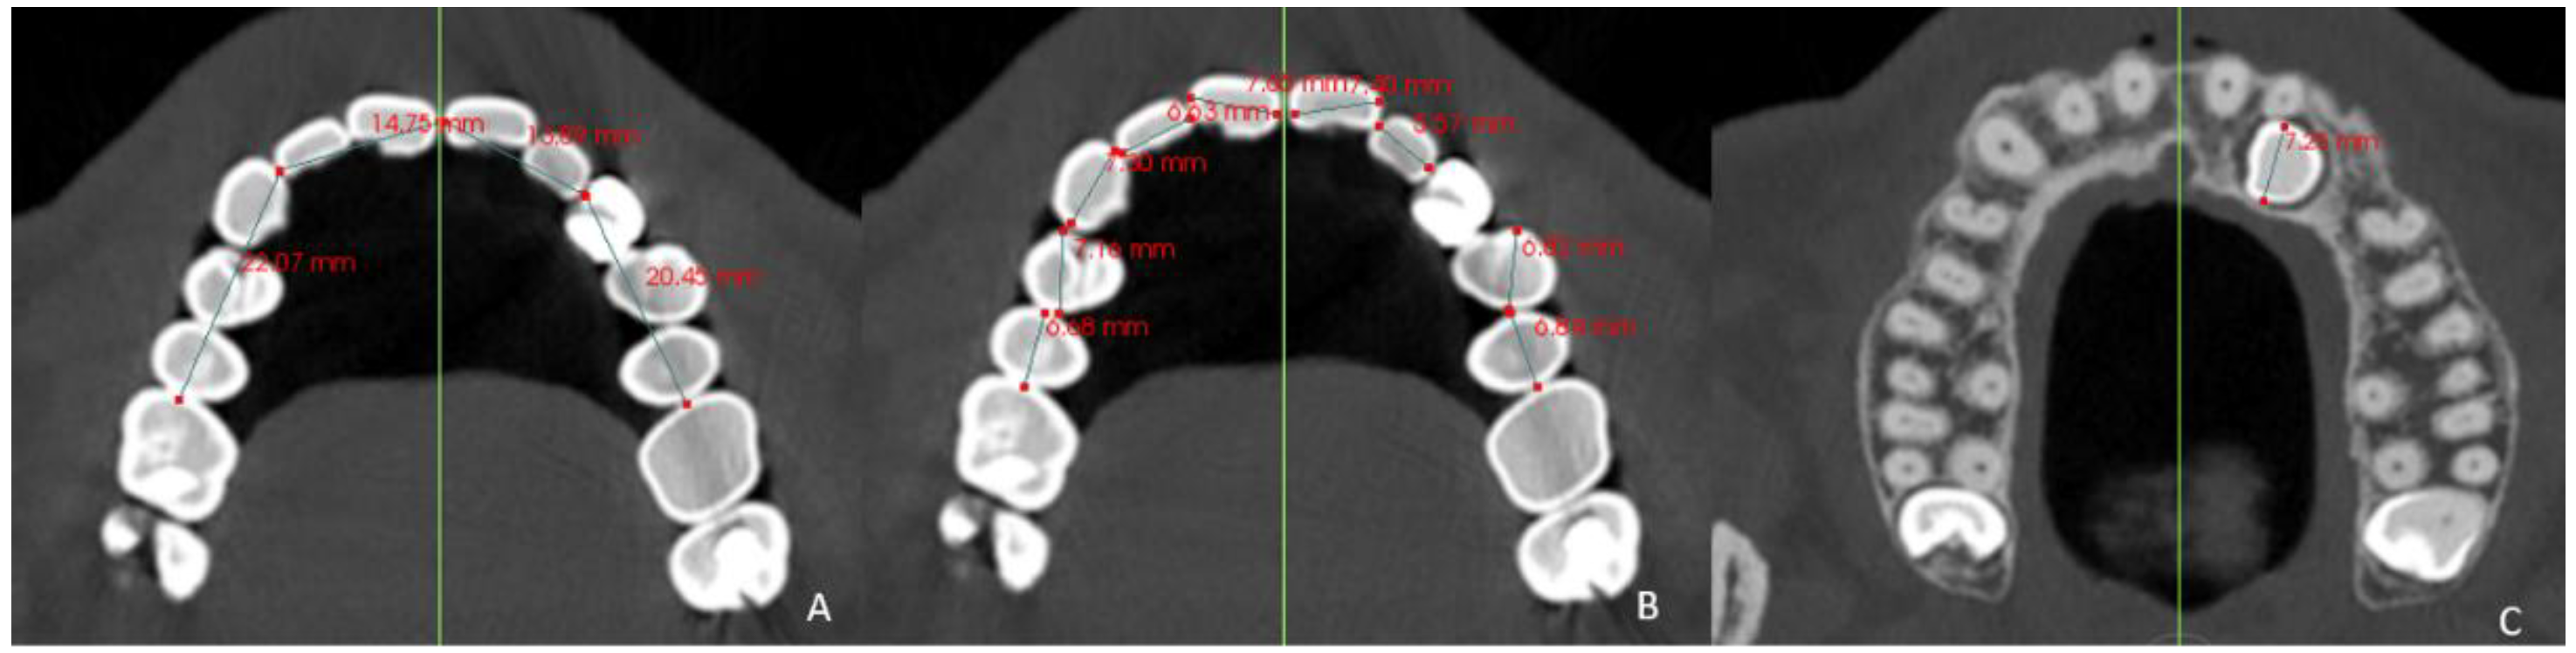

- Basal maxillary width (BMW) in the frontal plane, measured in the JL-JR Ricketts distance in the GC and GI (linear measurement between points on the jugal process at the intersection of the outline of the maxillary tuberosity and the zygomatic buttress) [26] and in the GI-R and GI-L, the JR and JL distance to the median palatal raphe (J-PR) (Figure 1).

- Arch length (AL) from mesial of the first permanent molar on one side to mesial of the first permanent molar on the contralateral side [35] in the GI and GC. In the GI-R and GI-L, from mesial of the first permanent molar on one side to the dental midline and from the dental midline to the mesial side of the contralateral first permanent molar (AL′) was measured (Figure 5).